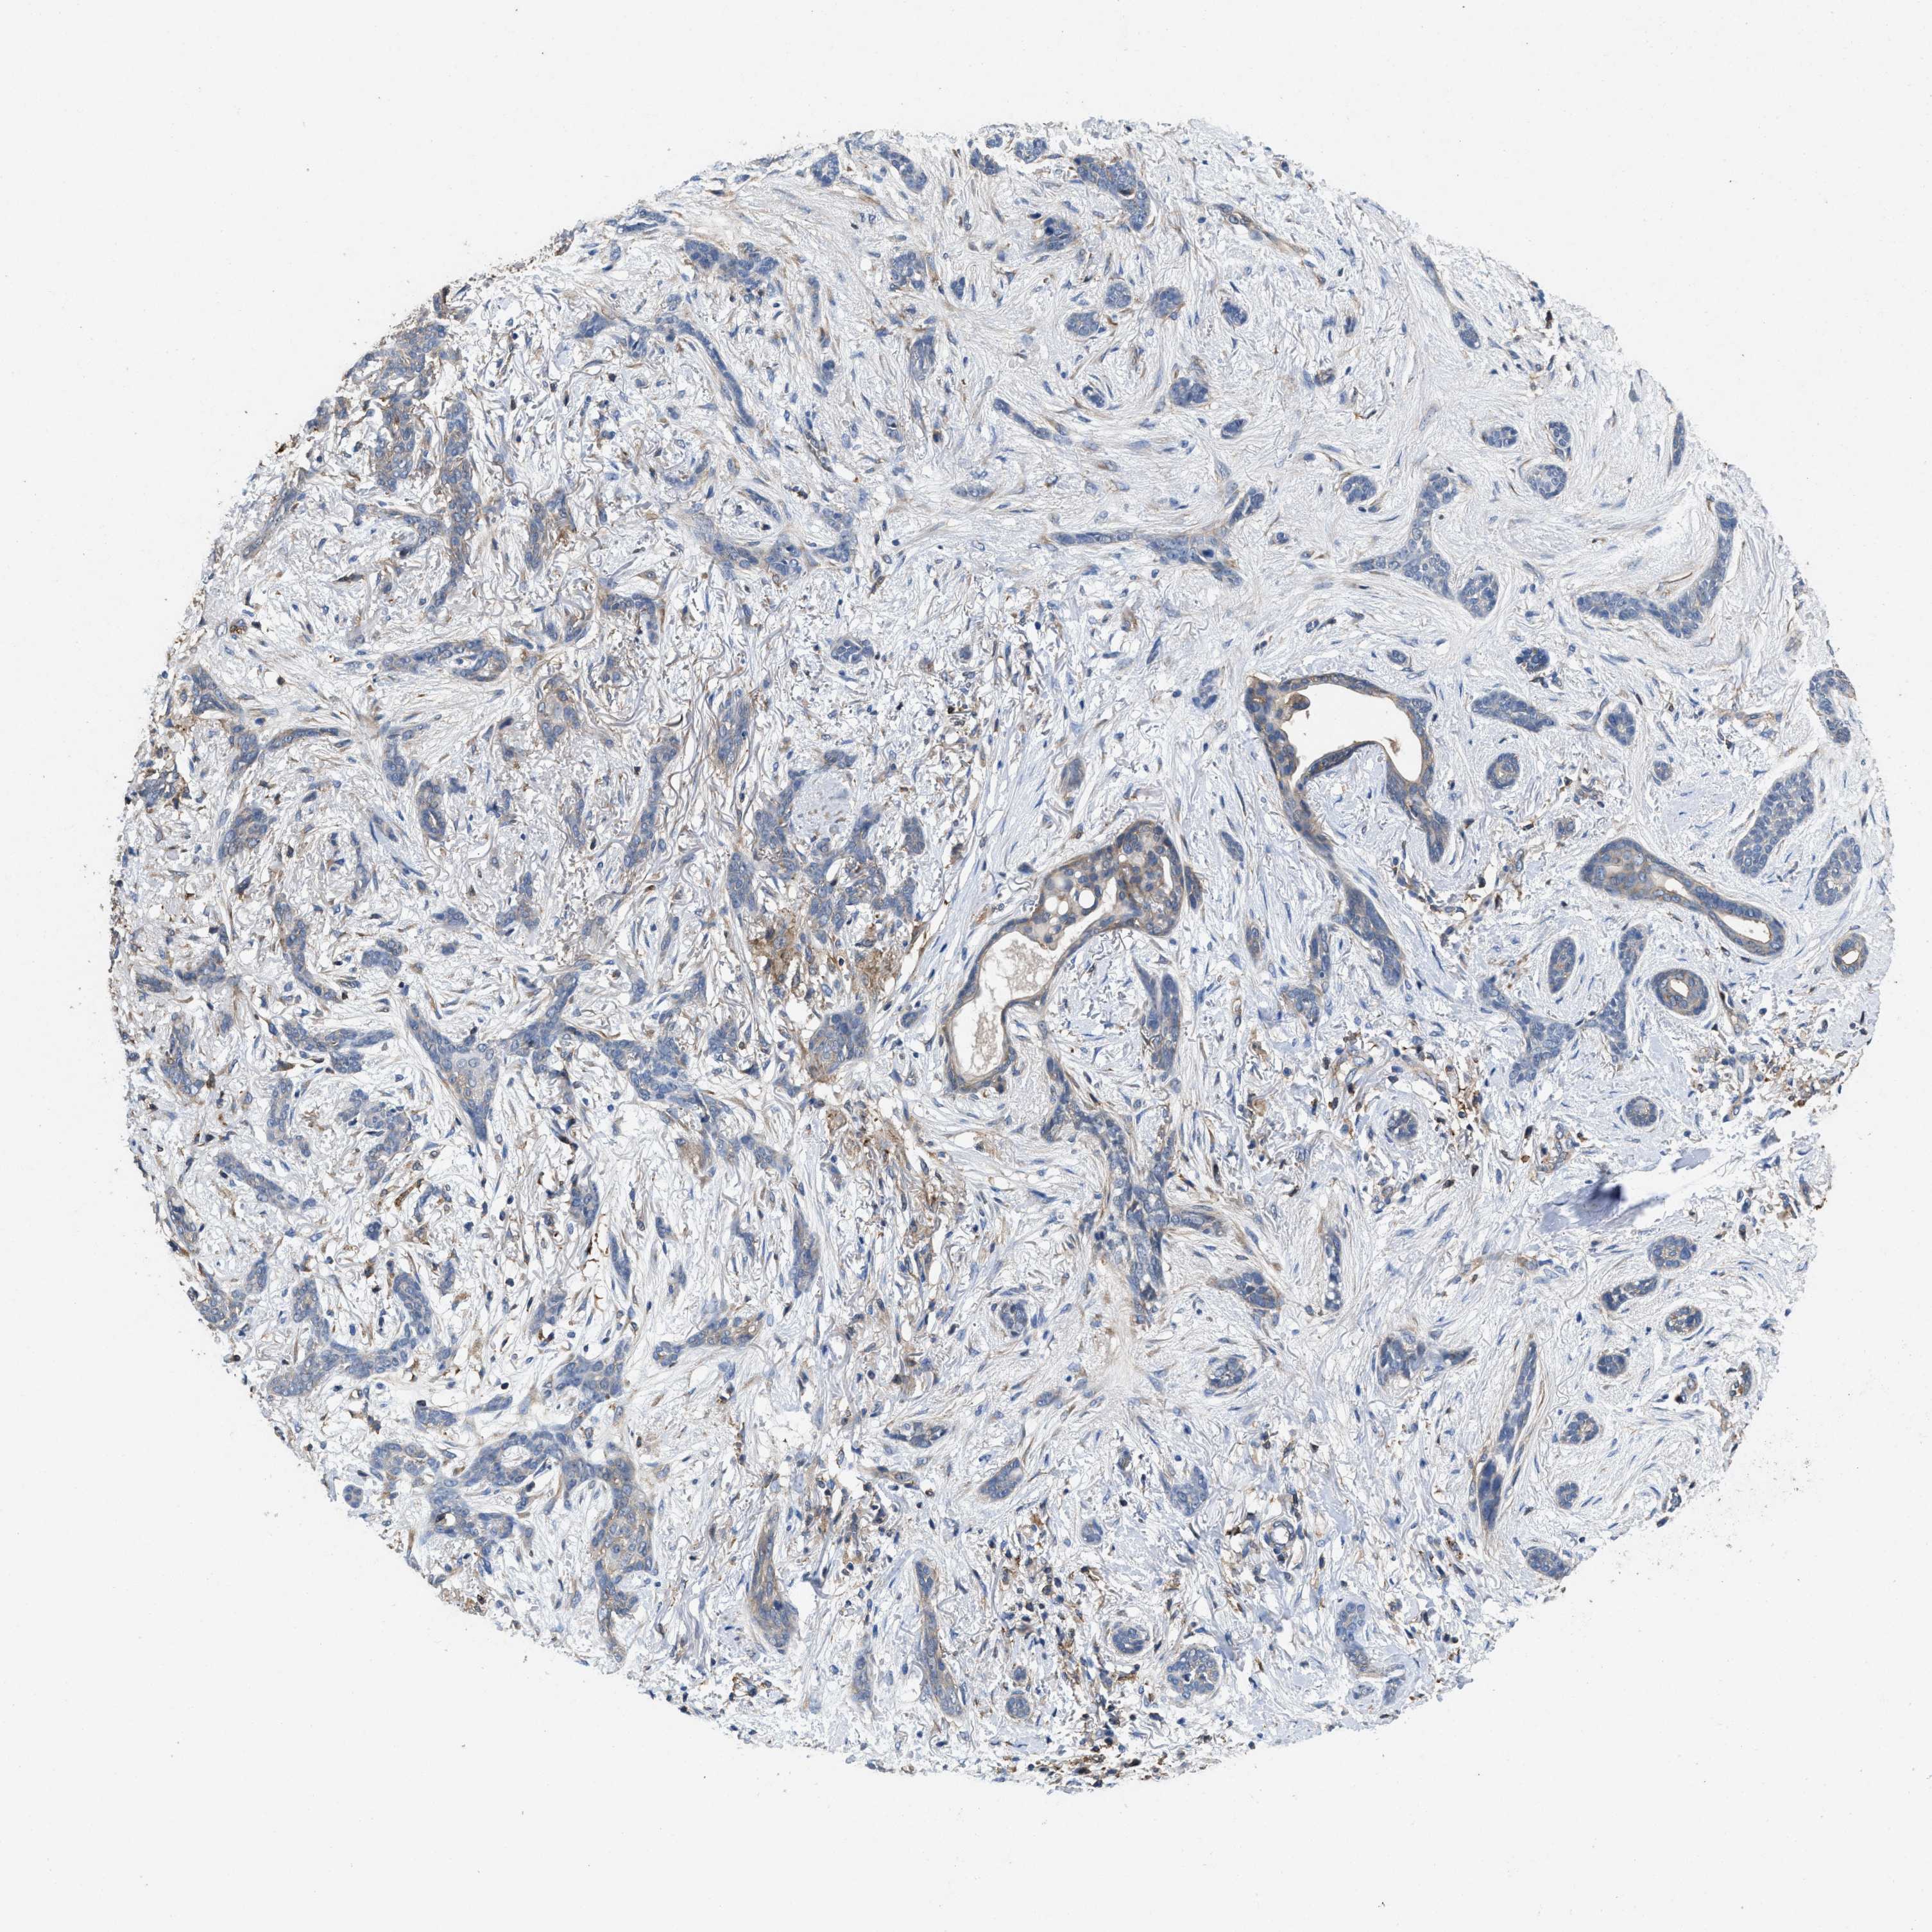

SKIN CANCER - Protein expressioni

A mouse-over function shows sample information and annotation data. Click on an image to view it in a full screen mode. Samples can be filtered based on level of antibody staining by selecting one or several of the following categories: high, medium, low and not detected. The assay and annotation is described here.

Antibody stainingi

Antibody staining in the annotated cell types in the current human tissue is reported as not detected, low, medium, or high, based on conventional immunohistochemistry profiling in selected tissues. This score is based on the combination of the staining intensity and fraction of stained cells.

Each image is clickable and will lead to virtual microscopy that enables deeper exploration of all samples and also displays staining intensity scores, fraction scores and subcellular localization as well as patient and tissue information for each sample.

Antibody HPA016633

Medium

Strong

75%-25%

Cytoplasmic/membranous

Squamous cell carcinoma, metastatic, NOS